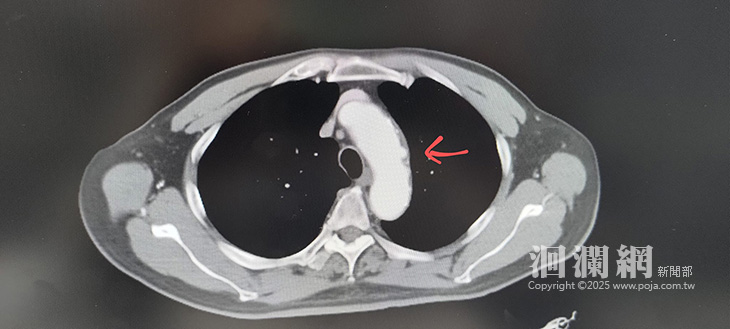

黃振銘表示,民眾常無法釐清上腹痛與胸痛差異,不同症狀足以影響醫師判斷,關乎生死。吳先生先到腸胃科就診,醫師擔心有其他潛在病因,幫他安排全身電腦斷層,意外發現主動脈弓上有穿透性主動脈潰瘍,有可能導致續發性主動脈剝離、血腫,甚至主動脈破裂而出血死亡。

一旦主動脈潰瘍出現胸痛、背痛、腹痛等症狀時,就代表主動脈潰瘍處承受不住血流的衝擊,可能即將出現主動脈剝離、血腫或破裂出血,要立刻控制血壓,儘快安排手術。黃振銘主刀以「微創挖洞式人工血管主動脈支架合併分支支架置放」,順利蓋掉主動脈弓上的潰瘍,也保留了左鎖骨下動脈的血流,手術成功。